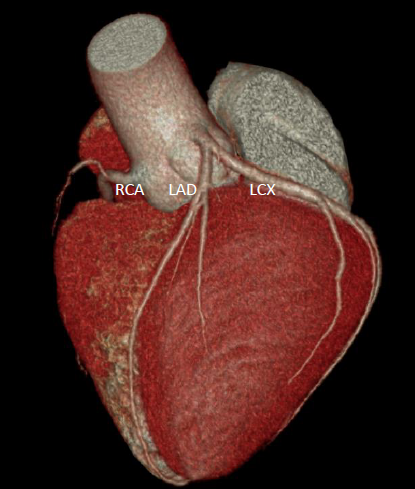

A 45-year-old man with no cardiac history presented with palpitations and frequent premature ventricular contractions (PVCs) on routine examination. Physical examination revealed irregular rhythm. Electrocardiography (ECG) demonstrated frequent PVCs with morphology suspected to originate from the right ventricular outflow tract (RVOT). Laboratory tests were unremarkable. 24-hour Holter monitoring showed a 40% PVC burden. Multidetector computed tomography (MDCT) revealed no coronary plaque.

By integrating the MDCT coronary anatomy with the three-dimensional electroanatomical map and ablation lesion sites, it was demonstrated that the radiofrequency applications were directly adjacent to the proximal LAD, resulting in thermal injury and IMH formation.